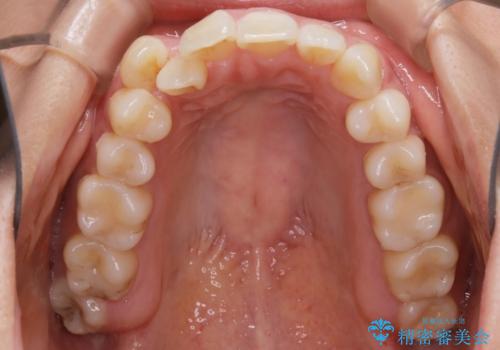

【非抜歯】インビザライン 隠れた前歯を並べる矯正治療

- 前歯のガタつき・奥に隠れてしまっている歯の矯正治療を希望されて初診来院されました。

顔貌的に口元を下げたいといった希望はなく抜歯はなるべく避けたいとのご要望からマウスピース装置(インビザライン)での治療を行うこととなりました。

非抜歯で矯正を行う場合にガタつきの改善に必要なスペースを作るために歯の遠心移動を行います。

最初の位置から奥に歯を移動させていくことで前歯のガタつきを改善したり、前歯の位置を後方に移動させることが可能となります。